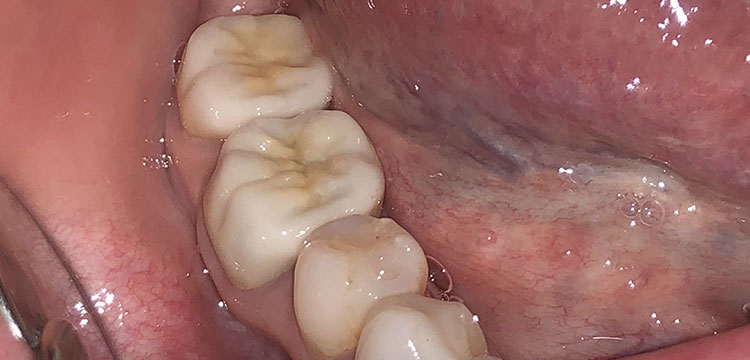

プレスセラミックの症例写真

5番の虫歯の治療を行いました。長持ちする材料、目立たない材料がご希望だった為、プレスセラミックで修復しました。

- 材 質……

プレスセラミックインレー

- 費 用……

1本 77,000円(税込)